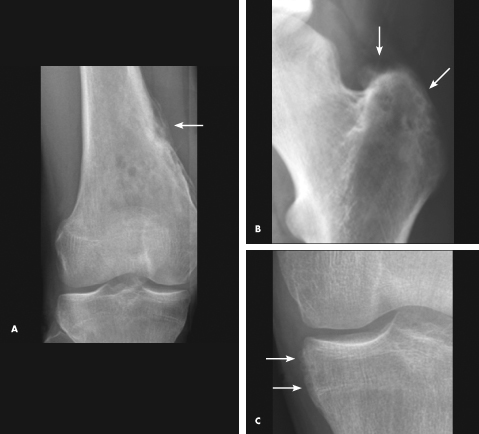

A radiograph of the right knee showed periosteal reaction of the medial aspect of the distal femur and focal lucencies and sclerosis in the metaphysis (A). Radiographs of the left pelvis and knee showed enthesopathy with bony proliferation change on the left greater trochanter (B) and left medial tibial plateau (C).